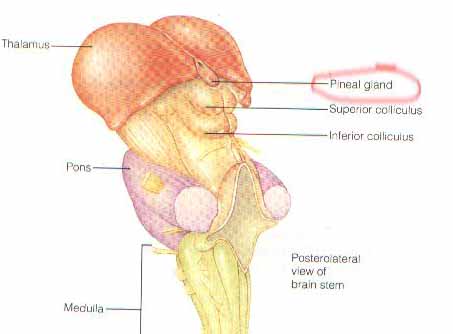

عجز العلماء عن معرفة هذه القوة الخارقة التي يمتلكها الإنسان بعد اندماج الروح بالجسد . ولايمر يوم من أيام الدنيا إلا والدراسات والاكتشافات العجيبة تخرج عن تلك القوى التي يمتلكها هذا العقل . ولما عكفوا على دراسة العقل لم يجدوا السر داخل المخ المرئي حتى بعد تشريحه وتصويره ومتابعته، فخلصوا إلى وجود عقل أكثر عمقا غير مرئي ولا ملموس ولا مسموع تنطلق منه أوامر الروح ، وأسموه بالعقل الباطن أو بالعقل اللاواعي .

الرسالة و يعدلها لكي نري الصورة بالمعدول . لكن الانسان له عين فزيائية أخري فائدتها ظلت غير معروفة للبشرية .

الرسالة و يعدلها لكي نري الصورة بالمعدول . لكن الانسان له عين فزيائية أخري فائدتها ظلت غير معروفة للبشرية .